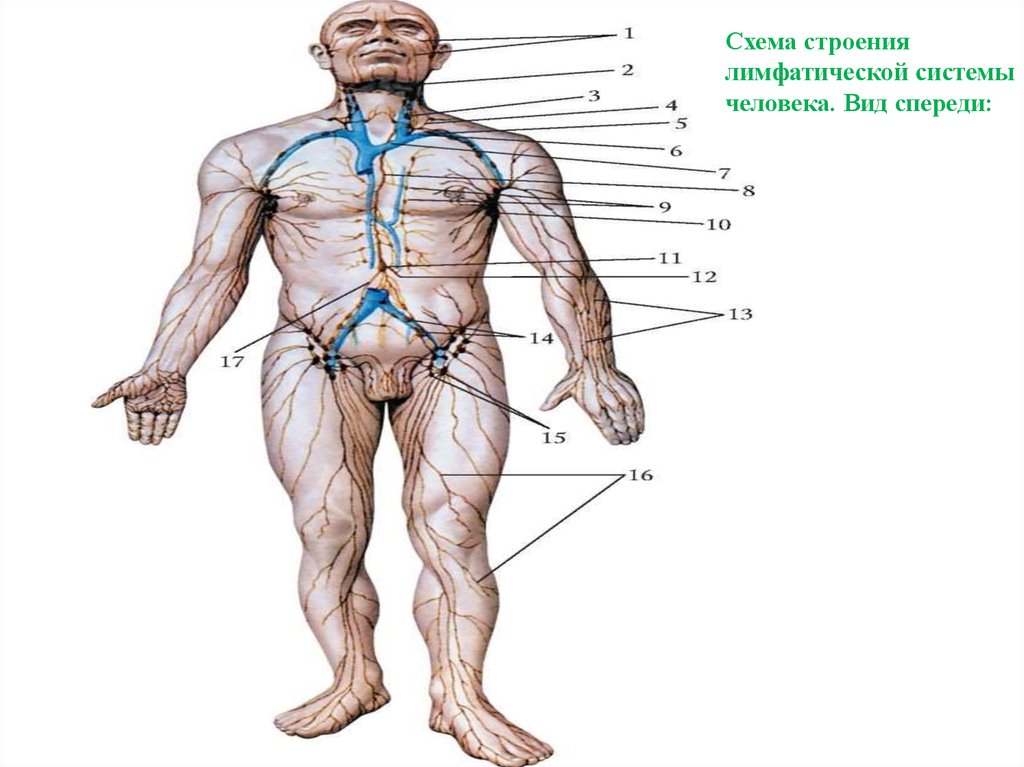

Изображения и схемы: как выглядит лимфа